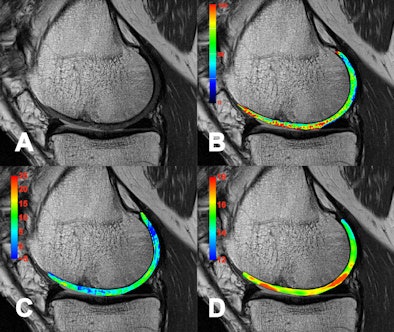

| A collection of images in a patient eight years after autologous osteochondral transplantation. Besides a standard morphological image (A) which shows minor defects in the transplantation area, several compositional (biochemical) MR methods are presented. T2 mapping (B) is collagen and water-specific, while chemical exchange saturation transfer (CEST) (C) and sodium imaging (D) are proteoglycan-specific MR methods. All biochemical methods reveal alterations in the normal structure of the cartilage transplant. So far CEST and Sodium (23Na) imaging can only be performed with 7-tesla MR scanners. |